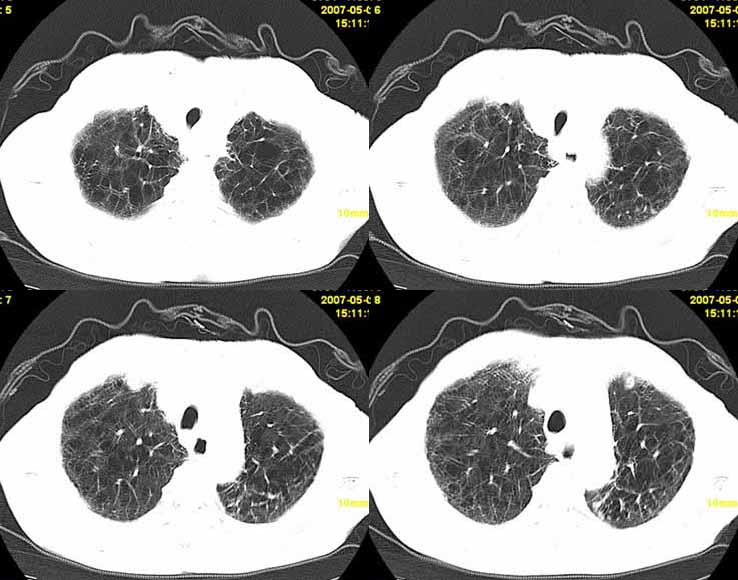

以下是引用小初学者在2007-5-12 11:09:00的发言:[br][br]双肺弥漫性质纤维化(考虑矽肺所致),并发左肺下叶背段周围性肺癌纵隔淋巴转移。

以下是引用zhangzhongshou在2007-5-12 12:09:00的发言:[br]1、左下叶背段周围型肺癌左肺门及纵隔淋巴结转移可能性大。[br]2、弥漫性肺气肿(双侧)。[br]3、双肺间质纤维化。

以下是引用老爱克斯新网客在2007-5-12 12:54:00的发言:[br]1周围型肺癌纵隔肺门淋巴结转移,2肺间质纤维化,